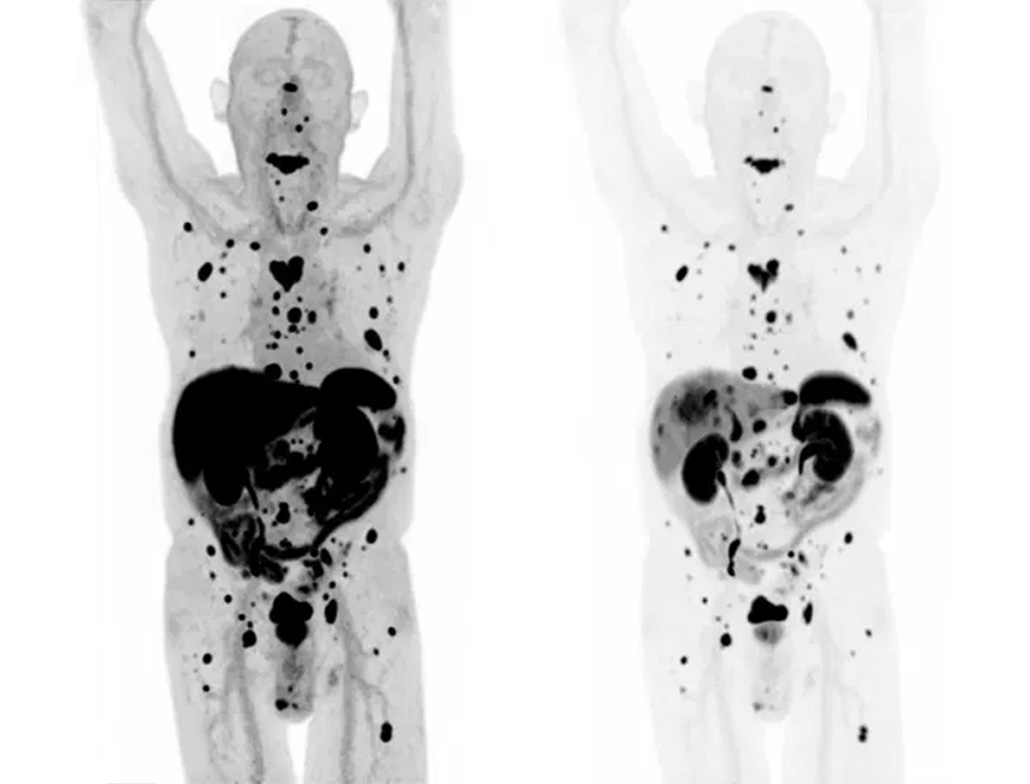

01. 18F‑FDG

Maps glucose metabolism to help find and monitor cancers; also used in heart viability and certain brain conditions for functional assessment.